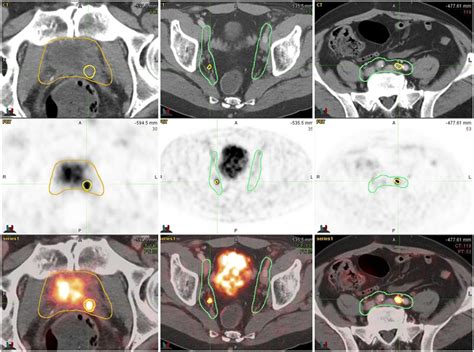

FCH PET/CT: Local recurrence of prostate cancer after ... from www.researchgate.net Prostate cancer is caused by changes in the genes of a normal prostate cell. Overall, a man who has undergone prostatectomy for localized prostate cancer has a 10 to 30 percent chance of experiencing prostate cancer recurrence during his lifetime. Prostate cancer symptoms can include difficulty urinating, frequent urination, pain while urinating, and a what are the early warning signs and symptoms of prostate cancer? If prostate cancer is suspected, a physical examination and the following tests may be used to decide if more diagnostic tests are needed for example, sodium fluoride is absorbed by bones, and its use in a pet scan may improve the chances of finding prostate cancer that has spread to the bone. Among these cases of recurrence, about half happen during the first three years after. The prostate is a gland in the male reproductive system that surrounds the urethra just below the bladder. Recurrent prostate cancer is when your cancer comes back after you've had a treatment that aimed to cure it. Risks of radiotherapy include cancer recurrence, erectile dysfunction, urinary symptoms such as frequency, urgency and difficulty voiding.